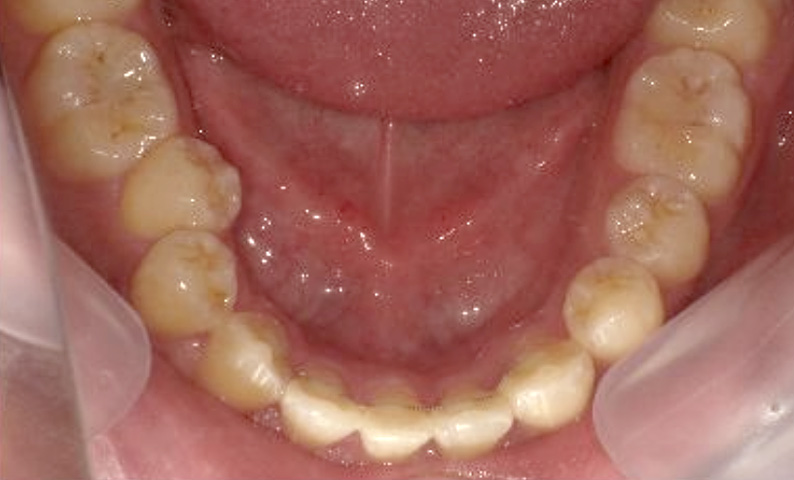

症例_002 下顎だけの部分矯正

治療期間:4ヶ月金額:30万円+税女性前歯のガタガタ下の前歯だけ

| Before | After |

|---|---|

|